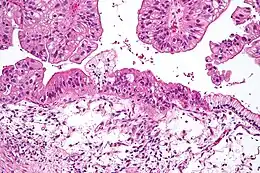

Anatomopathologie

Classification anatomopathologique

Classification histopathologique des carcinomes épithéliaux de l'ovaire (OMS)

- Cystadénocarcinome séreux (42 %)

- Carcinome endométrioïde (15 %)

- Carcinome à cellules claires (6 %), de mauvais pronostic

- Cystadénocarcinome mucineux, rares et de mauvais pronostic[19]

- Carcinome indifférencié

- Tumeur mixte épithéliale

Lésions non épithéliales

- Tumeur de Brenner

- Tumeur germinale

- Tumeur des cordons sexuels (HCG)

- Tumeur de Krukenberg

- Tumeur non classée

Les lésions de Krukenberg sont des métastases ovariennes d'un adénocarcinome d'une autre origine (estomac, sein). Le carcinome séreux du péritoine se traite comme un carcinome épithélial de l'ovaire